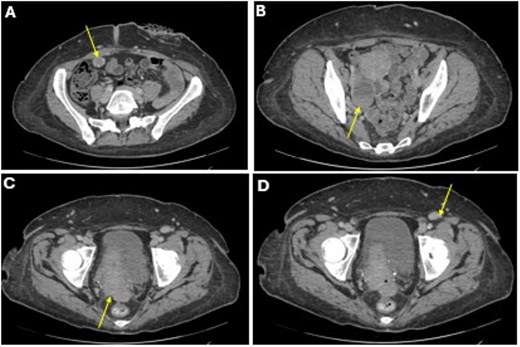

She completed six cycles of adjuvant leucovorin/folinic acid, 5-fluorouracil, and oxaliplatin (FOLFOX) before developing pelvic and perineal discomfort. CT imaging demonstrated suspicious masses of the right abdominal wall (Fig. 1A), right ovary (Fig. 1B), anterior rectum (Fig. 1C), and left inguinal lymph node (Fig. 1D). A fine needle aspiration of the peritoneum and cervix confirmed metastatic colorectal adenocarcinoma. Given the progression despite being on chemotherapy, a multidisciplinary discussion was made to initiate pembrolizumab. The patient completed 1 year of therapy (20 cycles), which she tolerated well. Restaging with esophagogastroduodenoscopy (EGD), colonoscopy, and positron emission tomography (PET) demonstrated stable disease without progression (Fig. 2). MRI imaging redemonstrated essentially stable appearing right rectus abdominus muscle mass measuring 2.1 × 1.6 × 2.2 cm (Fig. 3A), two suspicious ovarian lesions measuring 2.9 × 1.7 × 3.2 and 2.0 × 1.2 × 1.9 cm (Fig. 3B), an additional mass abutting the anterior peritoneal reflection measuring 3.7 × 2.9 × 3.1 cm (Fig. 3C), and prominent 12 mm left inguinal lymph node (Fig. 3D).

A CT imaging showing lesions involving the right abdominal wall (A), right ovary (B), right anterior reflection of the rectum (C), and left inguinal lymph node (D).